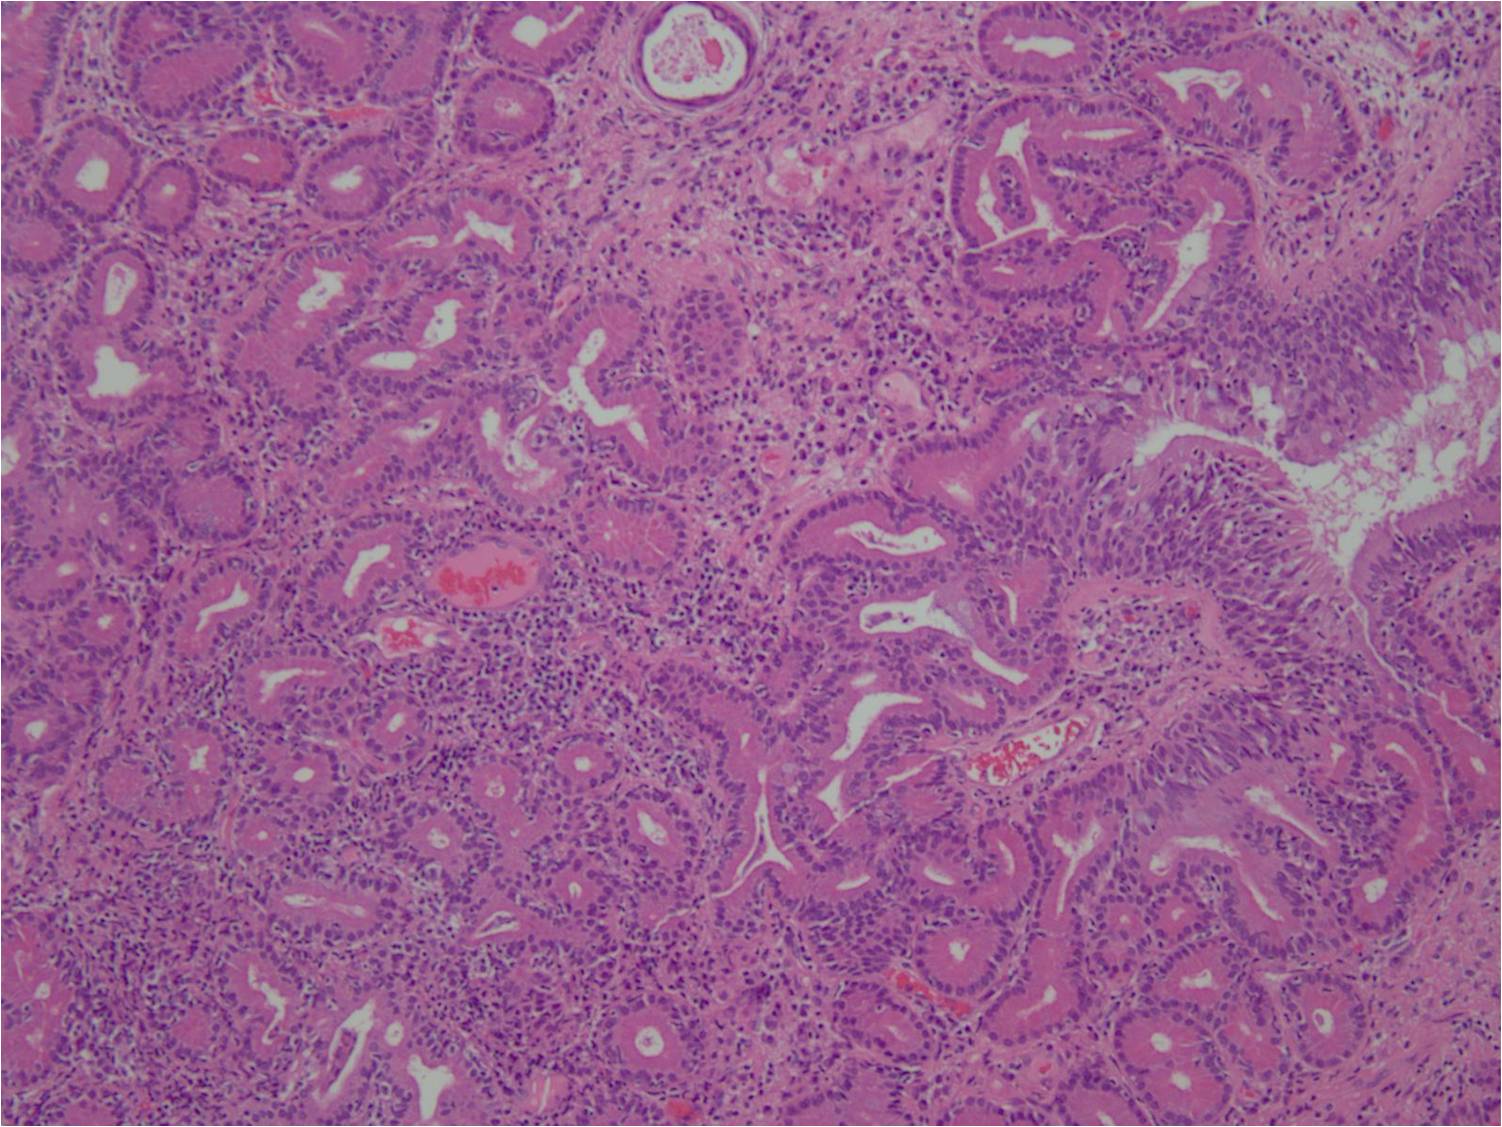

Карнификация Легкого: Микропрепараты и Диагностика

Раздел: Калейдоскоп образов